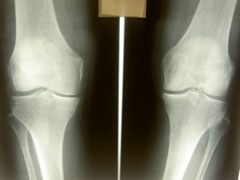

変形性膝関節症、鵞足炎、タナ障害、膝蓋軟骨軟化症、離断性骨軟骨炎、十字靭帯損傷、半月板損傷、靭帯損傷、スポーツ障害、成長痛(オスグット)などたくさんありますが一般的に膝の痛みで年配の方に多いは変形性膝関節症でしょうか?

歩行や運動時に痛み、だるさ、腫脹、可動域制限などの症状があります。

これは膝自体にも炎症があり、また同時に太ももの筋肉によって膝の関節同士が引き寄せられてしまっていることが多いです。そういう状態になってしまうには膝だけでなく足首や股関節・骨盤に問題があることがあります。膝に痛みがある時でも足から身体全体を施術して膝に負担のかからない身体を作ることによって膝関節の水腫も早期に引いて再発しにくくなります。